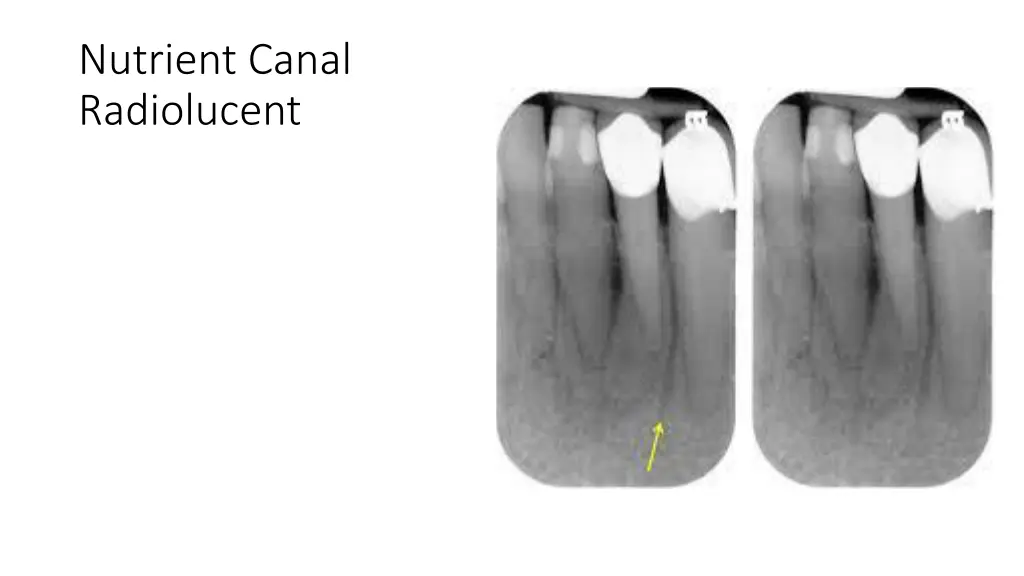

Nutrient Canal Radiolucent